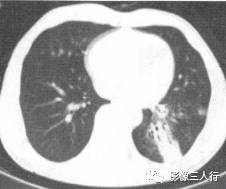

胸部CT图像显示,在含气少的致密肺的背景上见到含气的支气管,表现为两种形态: ①在大片肺实变病灶内的细条状空气密度影;②直径Imm的小泡状空气密度影,连续的几 个层面都能出现(图2、图3)。该征象表明:①近侧气道通畅;②肺泡内的空气经吸收(肺不张)或取代(肺炎、肺癌),或两者综合而消失。通畅含气的支气管在肺泡实变高 密度区内表现为管腔内低密度充气轮廓。